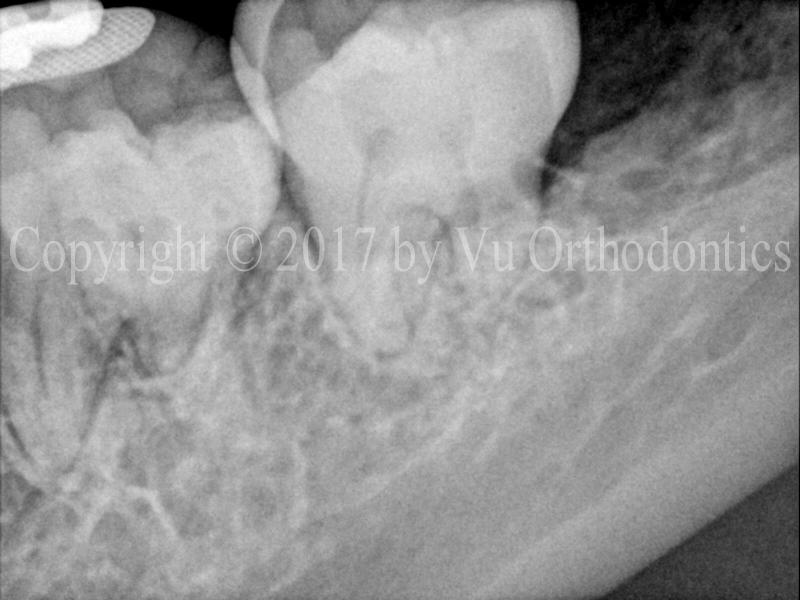

Figure 3 shows an example of the impacted lower left wisdom tooth (#17). The tooth is horizontally impacted and almost completely bony. The extraction was done without a bone graft. This type of bone graft is called socket graft. The result is, more than likely, that the lower left second molar (tooth #18) will suffer a bony defect on its distal side.

(a)

(b)

(c)

Fig. 3 Horizontally impacted lower left wisdom tooth (#17): (a) before extraction, (b) BW radiograph after extraction, without socket graft, (c) PA radiograph after extraction, without socket graft